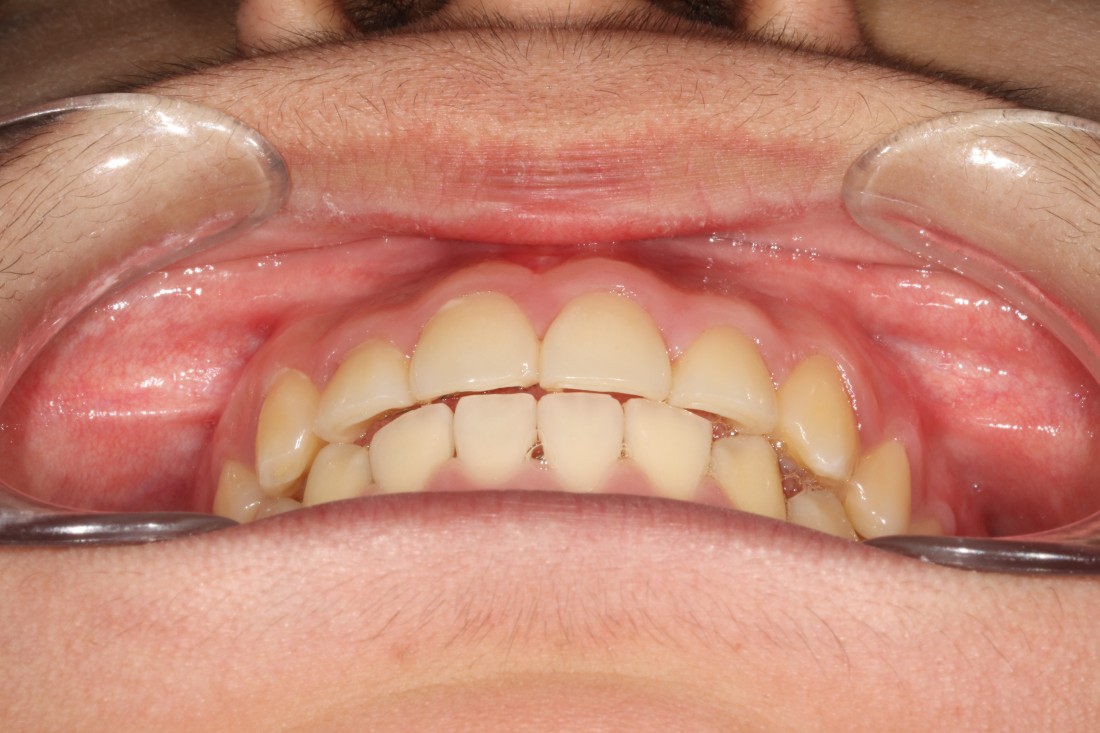

광주 덧니교정 치과는

대표원장인 제가 직접

다양한 교정 전/후 케이스를

공유하고 있습니다.

다양한 각도에서 촬영한

교정 전/후 사진을 직접 확인할 수 있어

광주 덧니교정 치과의

실력있는 진료를 증명하고 있습니다.

발치를 진행한 덧니교정이나

비발치 덧니교정 모두

다양한 케이스를 보유하고 있기 때문에

나의 구강구조와 비교해보면서

성공적인 교정치료 결과를

기대해보실 수 있습니다.